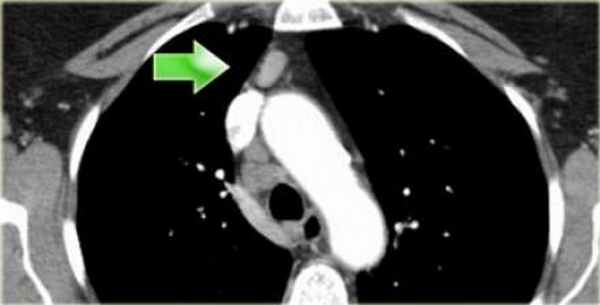

3. Праваскулярные и превертебральные лимфатические узлы

Лимфатические узлы 3 группы не примыкают к трахее в отличии от лимфатических узлов 2 группы.

Они подразделюятся на:

3А кпереди от сосудов

3Р позади пищевода/превертебрально

Они не доступны при медиастиноскопии. 3Р группа может быть доступна при чреспищеводной эхокардиографии.

На изображении слева 3А узел в преваскулярном пространстве. Обратите внимание так же на ниже расположенные паратрахеальные узлы справа относящиеся к 4R группе.